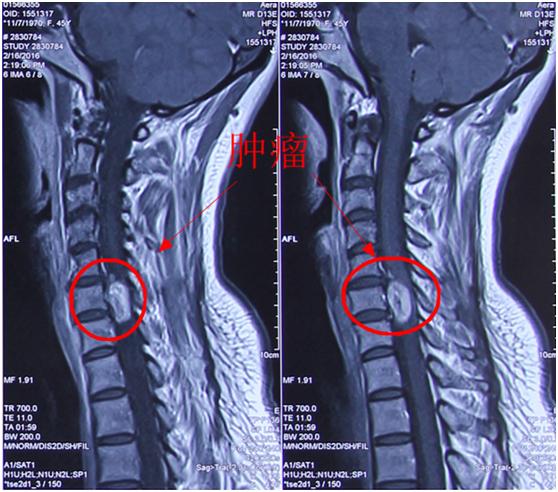

今年初,李老师上述症状再一次出现加重。就诊于某医院经查MRI被诊断为“颈椎管内占位性病变”。为进一步诊断、治疗,李老师选择第四军医大学唐都医院就诊。唐都医院神经外科脊柱脊髓疾病治疗组査颈椎MRI示:颈椎曲度变直,椎体边缘显毛糙、变尖,T2W1示C2-7椎间盘信号减低,C3/4、C4/5、C5/6、C6/7椎间隙平面蛛网膜下腔受压,平C6椎体水平椎管内可见1.7cm*0.9cm类圆形等略长T1等略短T2及压脂略高信号影,边界尚清楚,增强扫描明显强化,病灶与正常脊髓分界尚清楚,位于硬脊膜内脊髓右侧,横断面及冠状面示椎间孔增宽,病灶呈哑铃形自椎管跨椎管外。

影像学资料:

唐都医院神经外科脊柱脊髓疾病治疗组组长李维新教授指出,从患者病史和影像学检查来看为C6椎体平面椎管内髓外硬膜内占位性病变,多考虑神经鞘瘤,颈3-7椎间盘突出。